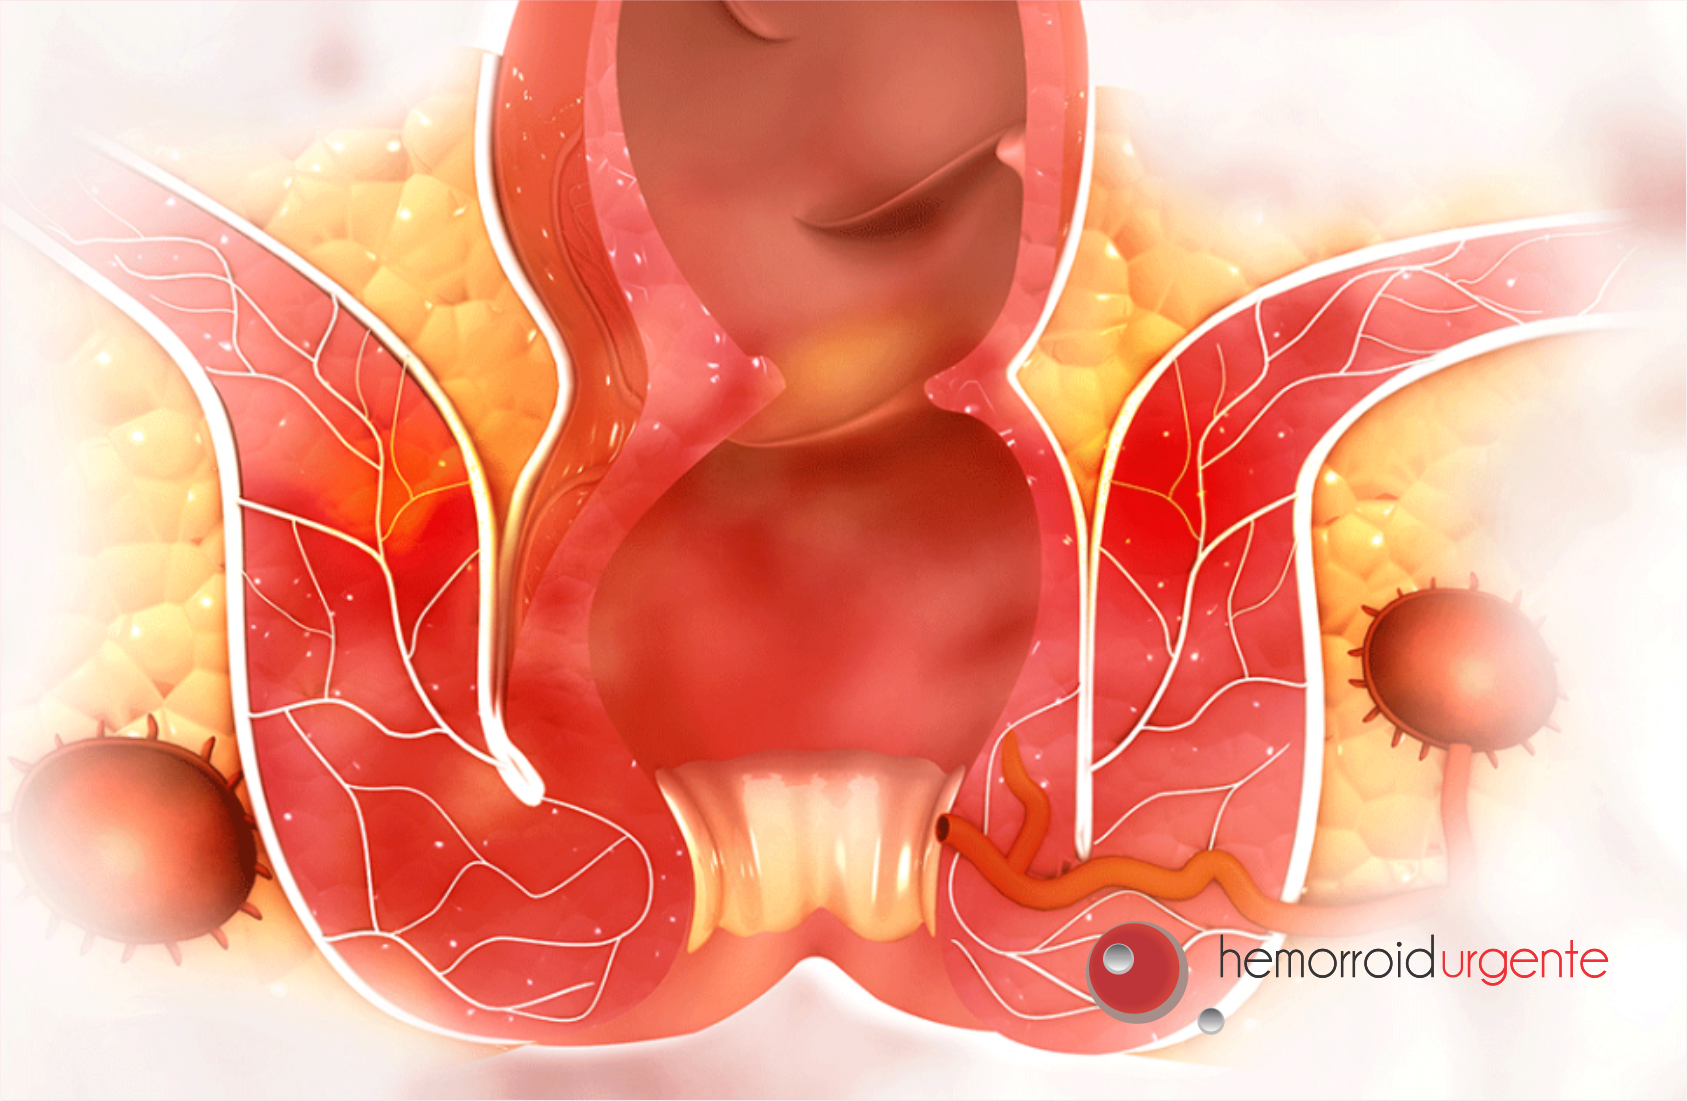

Hemorroida e doença hemorroidária são coisas diferentes, embora estejam diretamente ligadas. Para explicar melhor, vamos primeiro falar um pouco sobre os diversos tipos e evoluções da doença.

Existem quatro tipos de hemorroida, que vão desde o grau 1 (pequenas, raramente incomodam e se curam basicamente com cuidados diários e mudanças de hábitos) ao grau 4 (aspecto irregular do ânus, causa dor, dificuldade na evacuação e normalmente são casos cirúrgicos).

Vai além de uma crise de hemorroida. Algumas peles saem do ânus, que sofrem forte irritação, doem, coçam, incham, estufam e dificultam a higiene. Nesse caso, o melhor caminho é consultar um proctologista para tratar e evitar que piorem com o tempo.

Um outro ponto que merece destaque no assunto é a trombose hemorroidária. Ela acontece principalmente quando se tem uma hemorroida interna ou externa que se rompe ou fica comprimida pelo ânus, fazendo com que o sangue se acumule no ânus formando um coágulo, causando inchaço e intensa dor na região.

Quando a hemorroida se torna uma trombose hemorroidária, existe a possibilidade da veia de romper e vazar sangue coagulado e escuro, seguido de sangue vivo.